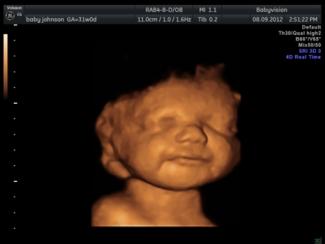

TELFORD, Veľká Británia, 15. január 2013 (LifeSiteNews.com) - Rodičia chlapca, ktorému diagnostikovali ťažkú malformáciu, odmietli radu podstúpiť potrat po tom, ako videli svoje dieťa sa usmiať, púšťať bubliny, mávať ručičkami a kopať počas 3D ultrazvuku v 20. týždni života.

„Zariadili ďalšie ultrazvukové vyšetrenia, aby posúdili rozsah jeho postihnutia, ale keď som ho videla usmievať sa a vyvádzať v mojom vnútri, vedela som, že nemôžem ukončiť jeho život,“ povedala Katyia.

Vysvetlila: „Napriek všetkým tým strašným veciam, ktoré mi hovorili, to vyzeralo, že kvalita jeho života v mojom brušku je úžasná a nie je iná ako u ostatných detí. Bola radosť naňho pozerať.“

„Povedali mi, že nikdy nebude chodiť alebo rozprávať, napriek tomu sa počas vyšetrenia neustále krútil a hýbal.